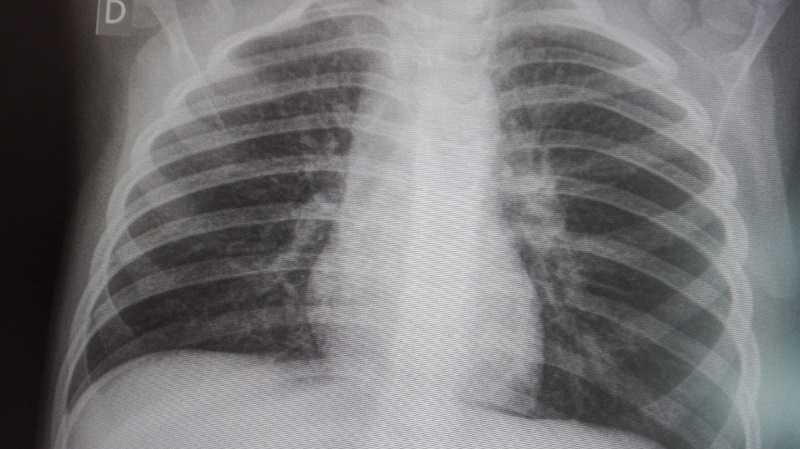

Se realizó una analítica sanguínea y radiografía de tórax, apareciendo un patrón alveolar en lóbulo inferior derecho (Fig. 1). En el hemograma destacó leucocitosis de 20 400 leucos/mm3, 4200 neutrófilos/mm3, velocidad de sedimentación globular (VSG) de 16 mm/hora, proteína C reactiva 0,3 mg/dl, y elevación de transaminasas y marcadores de inflamación hepática: GGT 261 U/l, GOT 147 U/l, GPT 235 U/l y LDH 764 U/l. Dada la sospecha radiológica de neumonía neumocócica, se inició tratamiento con amoxicilina a 80 mg/kg/día. Se realizó un aspirado nasofaríngeo para virus respiratorios por inmunofluorescencia directa que resultó negativo; y serologías, con IgM positivas para Mycoplasma pneumoniae (técnica rápida), VEB (automatizado por quimioluminiscencia) y parvovirus B19 (inmunofluorescencia indirecta). A las 48 horas la paciente estaba afebril, por lo que se completó pauta con amoxicilina.

| Figura 1. Radiografía anteroposterior con consolidación parenquimatosa en el lóbulo inferior derecho |

Las manifestaciones radiológicas de estos tres gérmenes son inespecíficas, sin embargo, se pueden destacar el patrón intersticial, atrapamiento aéreo y discreta participación pleural como más frecuentes1,3. Es por este motivo que llama la atención el patrón alveolar que presenta la paciente, típico de neumonía por Streptococcus pneumoniae (Fig. 1). Por ello, es importante resaltar la dificultad para determinar la etiología neumocócica y establecer la incidencia real de la neumonía por Streptococcus pneumoniae. Las técnicas utilizadas en adultos (serología, antigenuria) pierden especificidad en el caso de los niños, ya que no diferencian el estado de portador ni la inmunidad posvacunal lograda con las vacunas antineumocócicas conjugadas, lo que genera un gran número de falsos positivos. Muchos niños son portadores nasofaríngeos de Streptococcus pneumoniae durante los primeros años de vida, la colonización es un factor de riesgo para padecer la enfermedad. La duración del estado de portador varía y es en general más larga en niños que en adultos6,7.